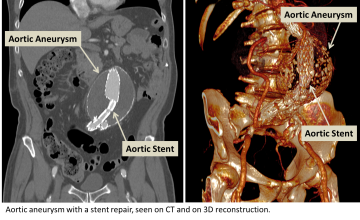

Endovascular stent grafting (EVAR, or endovascular aneurysm repair)

Endovascular stent grafting is a procedure that is performed to treat aneurysm or and dissection. A stent graft is an expandable vascular conduit which is placed into the diseased segment of vessel thereby reinforcing the vessel wall and reducing the potential of rupture or progression of disease.

• The procedure is performed by using a need to access a vessel in the arm or leg and placing wire into the vessel.  The wire is navigated into the aneurysmal or dissected vessel using a fluroscope (x-ray machine) to guide the navigation.

• Once the wire is properly placed, an appropriate stent graft is selected based on many factors including the size of the vessel, the types of branches that come from the diseased vessel, and the type of aneursym or dissection being treated.  The collapsed stent graft is fed into the target vessel using the wire and fluoroscope as a guide.

• Once the stent graft is appropriately positioned, a balloon is placed over the wire and into the center to the collapsed stent and used to expand the stent to seat it against the vessel wall.

• Contrast may be injected into the vessel to test the fit and seating of the stent graft.  Once a satisfactory placement has been made, the wire and balloon are removed from the body and the puncture made in the arm or leg is sealed.  The patient is then taken to the recovery area for post-procedural observation.

Aortic aneurysm with a stent repair seen on CT and on 3D Reconstruction